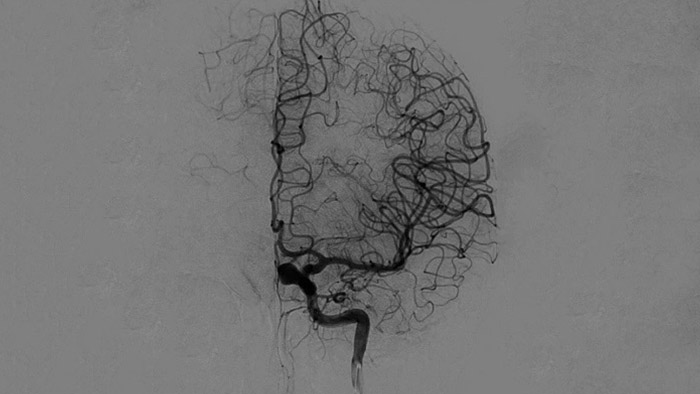

O ClarityIQ aplica uma Compensação Automática de Movimento durante a ASD em tempo real para manter imagens nítidas dos vasos, facilitando uma tomada de decisão confiante ao longo dos procedimentos de AVC.

As visualizações de ASD de alta qualidade permitem avaliar se você recuperou o coágulo inteiro e se pedaços do coágulo foram dispersados distalmente no cérebro. Você pode confirmar a restauração do fluxo sanguíneo para a penumbra e verificar se há sangramentos periprocedimento.

Tome decisões bem-fundamentadas quanto a se o coágulo pode ser alcançado e qual rota utilizar. O Roadmap Pro, um roteiro avançado de duplo contraste, ajuda a aprimorar a visualização de vasos superpostos e, ao mesmo tempo, equilibra a exposição à radiação.